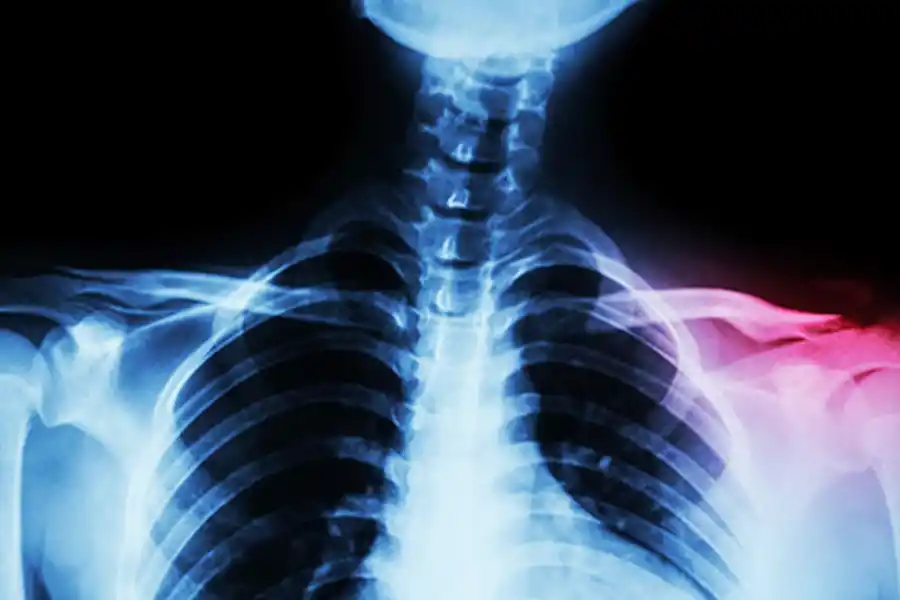

Una fractura de clavícula se diagnostica mediante un examen físico y radiografías.

Por su parte, Medline Plus, un servicio de la Biblioteca Nacional de Medicina de Estados Unidos, explica que la clavícula es un hueso largo y delgado ubicado entre la parte superior del tórax (esternón) y el hombro. Su función principal es brindar soporte y estabilidad a esta articulación.